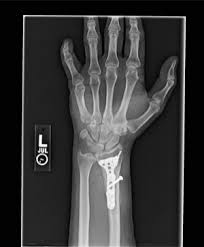

Recovering From A Distal Radius Fracture

Recovering From A Distal Radius Fracture from embed.widencdn.net